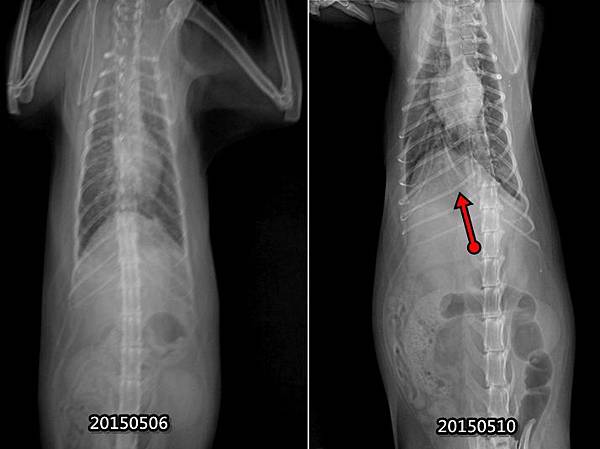

5月6日當天初診照的與5月10日照的肺部有一點不同(請看紅箭頭)

在這次就醫的醫院T醫師5月23日照的X光,其實就跟5月10日那天照的差不多

幾乎沒有什麼太大變化